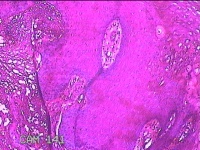

下唇肿物

性别

男

年龄

22岁

临床诊断

口腔黏液腺囊肿

下唇肿物一个月余。

大体所见

图1